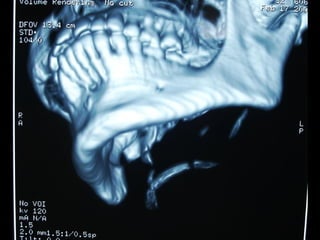

Eliminación de focos sépticos en bloque en paciente con osteitis

mandibular crónica

Osteitis

Imagen microscópica de osteitis, inicialmente existe una etapa de

osteoclastosis seguida por regeneración. No siempre el hueso

regenera en su totalidad y sigue el curso de cualquier inflamación

dejando un area de tejido fibroso que con el tiempo puede

calcificarse (hueso denso)

Manejo con antibióticos obligado

Revisión periódica